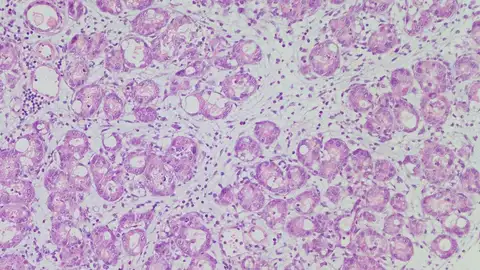

Científicos han descubierto una molécula que ayuda a madurar las células del páncreas y retrasa así los tumores de uno de los cáncer más agresivos.

Un equipo de investigadores ha descubierto una molécula que contribuye a madurar a las células del páncreas y que limita el desarrollo de tumores.

Los investigadores han descubierto que una molécula (llamada "NFIC") es clave para el correcto funcionamiento de esas células acinares, y el CNIO ha destacado que el hallazgo ayudará a entender qué ocurre cuando los procesos normales fallan y se originan el cáncer u otras lesiones.

En la publicación, los investigadores han determinado que si se desactiva esa molécula, las células acinares no maduran correctamente y el páncreas responde peor al daño y se vuelve más propenso a iniciar la formación de tumores.